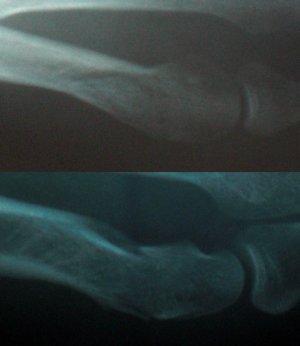

Снимок в реале не намного лучше, интересует место отмеченное кругом. Нога правая, верхнее фото - проекция с наружной стороны, нижнее фото - проекция сверху. Диагноз был поставлен перелом 5й плюсневой кости (без подробностей), впринципе по снимку это видно. поэтому и написал в этой теме. Подскажите тогда по выбору иммобилизации (и нужна ли она вообще) и ее срокам при таком повреждении.По такому плохому фото диагноз не ставят даже по снимку. Диагноз ставит врач при личном обращении пациента.

В данном случае какую иммобилизацию Вы бы рекомендовали и на какой срок? Работа связана с вождением автомобиля, т.е. давление на педали (нога правая). Когда можно приступать? После перелома полдня ездил нормально, до травмпункта доехал сам.Что то похожее на спиралевидный дистальный перелом.

35 лет. Рост 185. Вес 75. Как любитель занимаюсь активными видами спорта (виндсерфинг, сноуборд итд.). Перелом 17 марта от падения тяжелого предмета на стопу. Снимок сделан примерно через 3 часа.Я ведь про вас ничего не знаю, сколько лет,Ю ваша физическая форма, конституционный тип, время перелома...